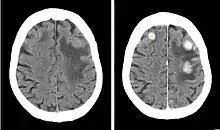

Iodinated contrast is a form of intravenous radiocontrast agent (radiographic dye) containing iodine, which enhances the visibility of vascular structures and organs during radiographic procedures. Some pathologies, such as cancer, have particularly improved visibility with iodinated contrast.

- Contrast CTs